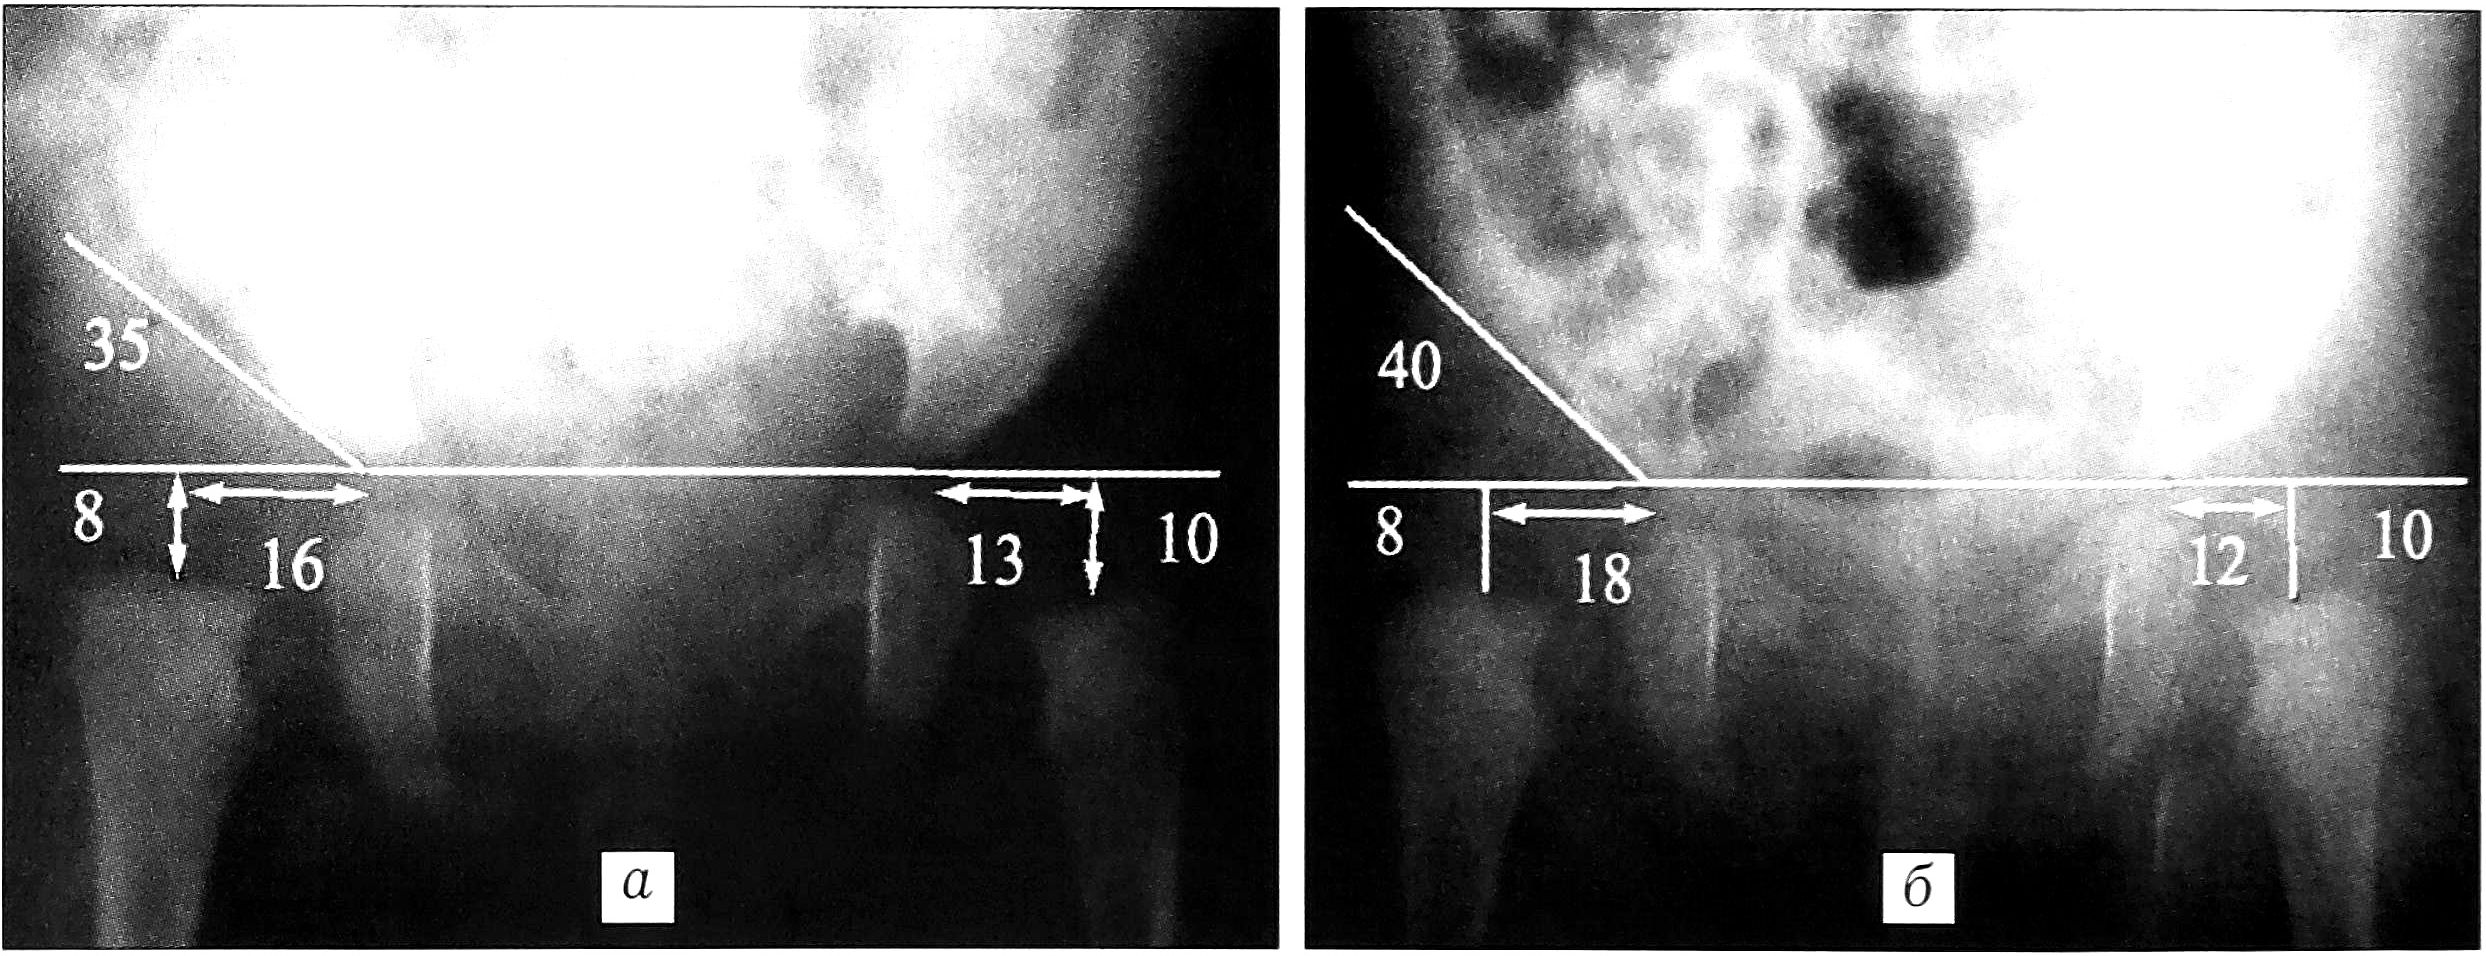

Из 35 пациентов, которым до поступления в ЦИТО проводилось лечение функциональной гипсовой повязкой, у 17 оно оказалось безуспешным. В большинстве случаев имело место нарушение методики лечения Тер-Егиазарова—Шептуна: вправление останавливалось на этапе разведения конечностей, тракция по оси бедра с целью выведения его головки из-за заднего края вертлужной впадины не производилась, при этом рентгенологический контроль осуществлялся не всегда. Так, больной Ч. лечение в функциональной гипсовой повязке было начато в возрасте 1 мес, а рентгенологический контроль впервые выполнен в 7 мес. Родители обратились с ребенком в ЦИТО в возрасте 1 года 3 мес (рис. 3).

Рис. 3. Пример неадекватного лечения в функциональной гипсовой повязке. Больная Ч., диагноз: врожденный надацетабулярный вывих головки левого бедра. а — в возрасте 1 мес; б — рентгенологический контроль в возрасте 7 мес в функциональной гипсовой повязке: головка левого бедра располагается за задним краем вертлужной впадины; в — при обращении в ЦИТО в возрасте 1 года 3 мес: вывих в левом тазобедренном суставе сохраняется.

Были и такие случаи (5,5%), когда при выявлении патологии лечение ограничивалось массажем и лечебной гимнастикой — без применения какого-либо ортопедического пособия. В конечном итоге это приводило к прогрессированию патологии, как, например, у больной М., у которой за 2 мес так называемой терапии произошло увеличение степени дисплазии (рис. 4).

Рис. 4. Пример неадекватного лечения при помощи массажа и лечебной гимнастики. Больная М., диагноз: врожденный вывих правого бедра. а — в возрасте 1 мес; б — рентгенологический контроль в возрасте 3 мес: прогрессирование дисплазии правого тазобедренного сустава.